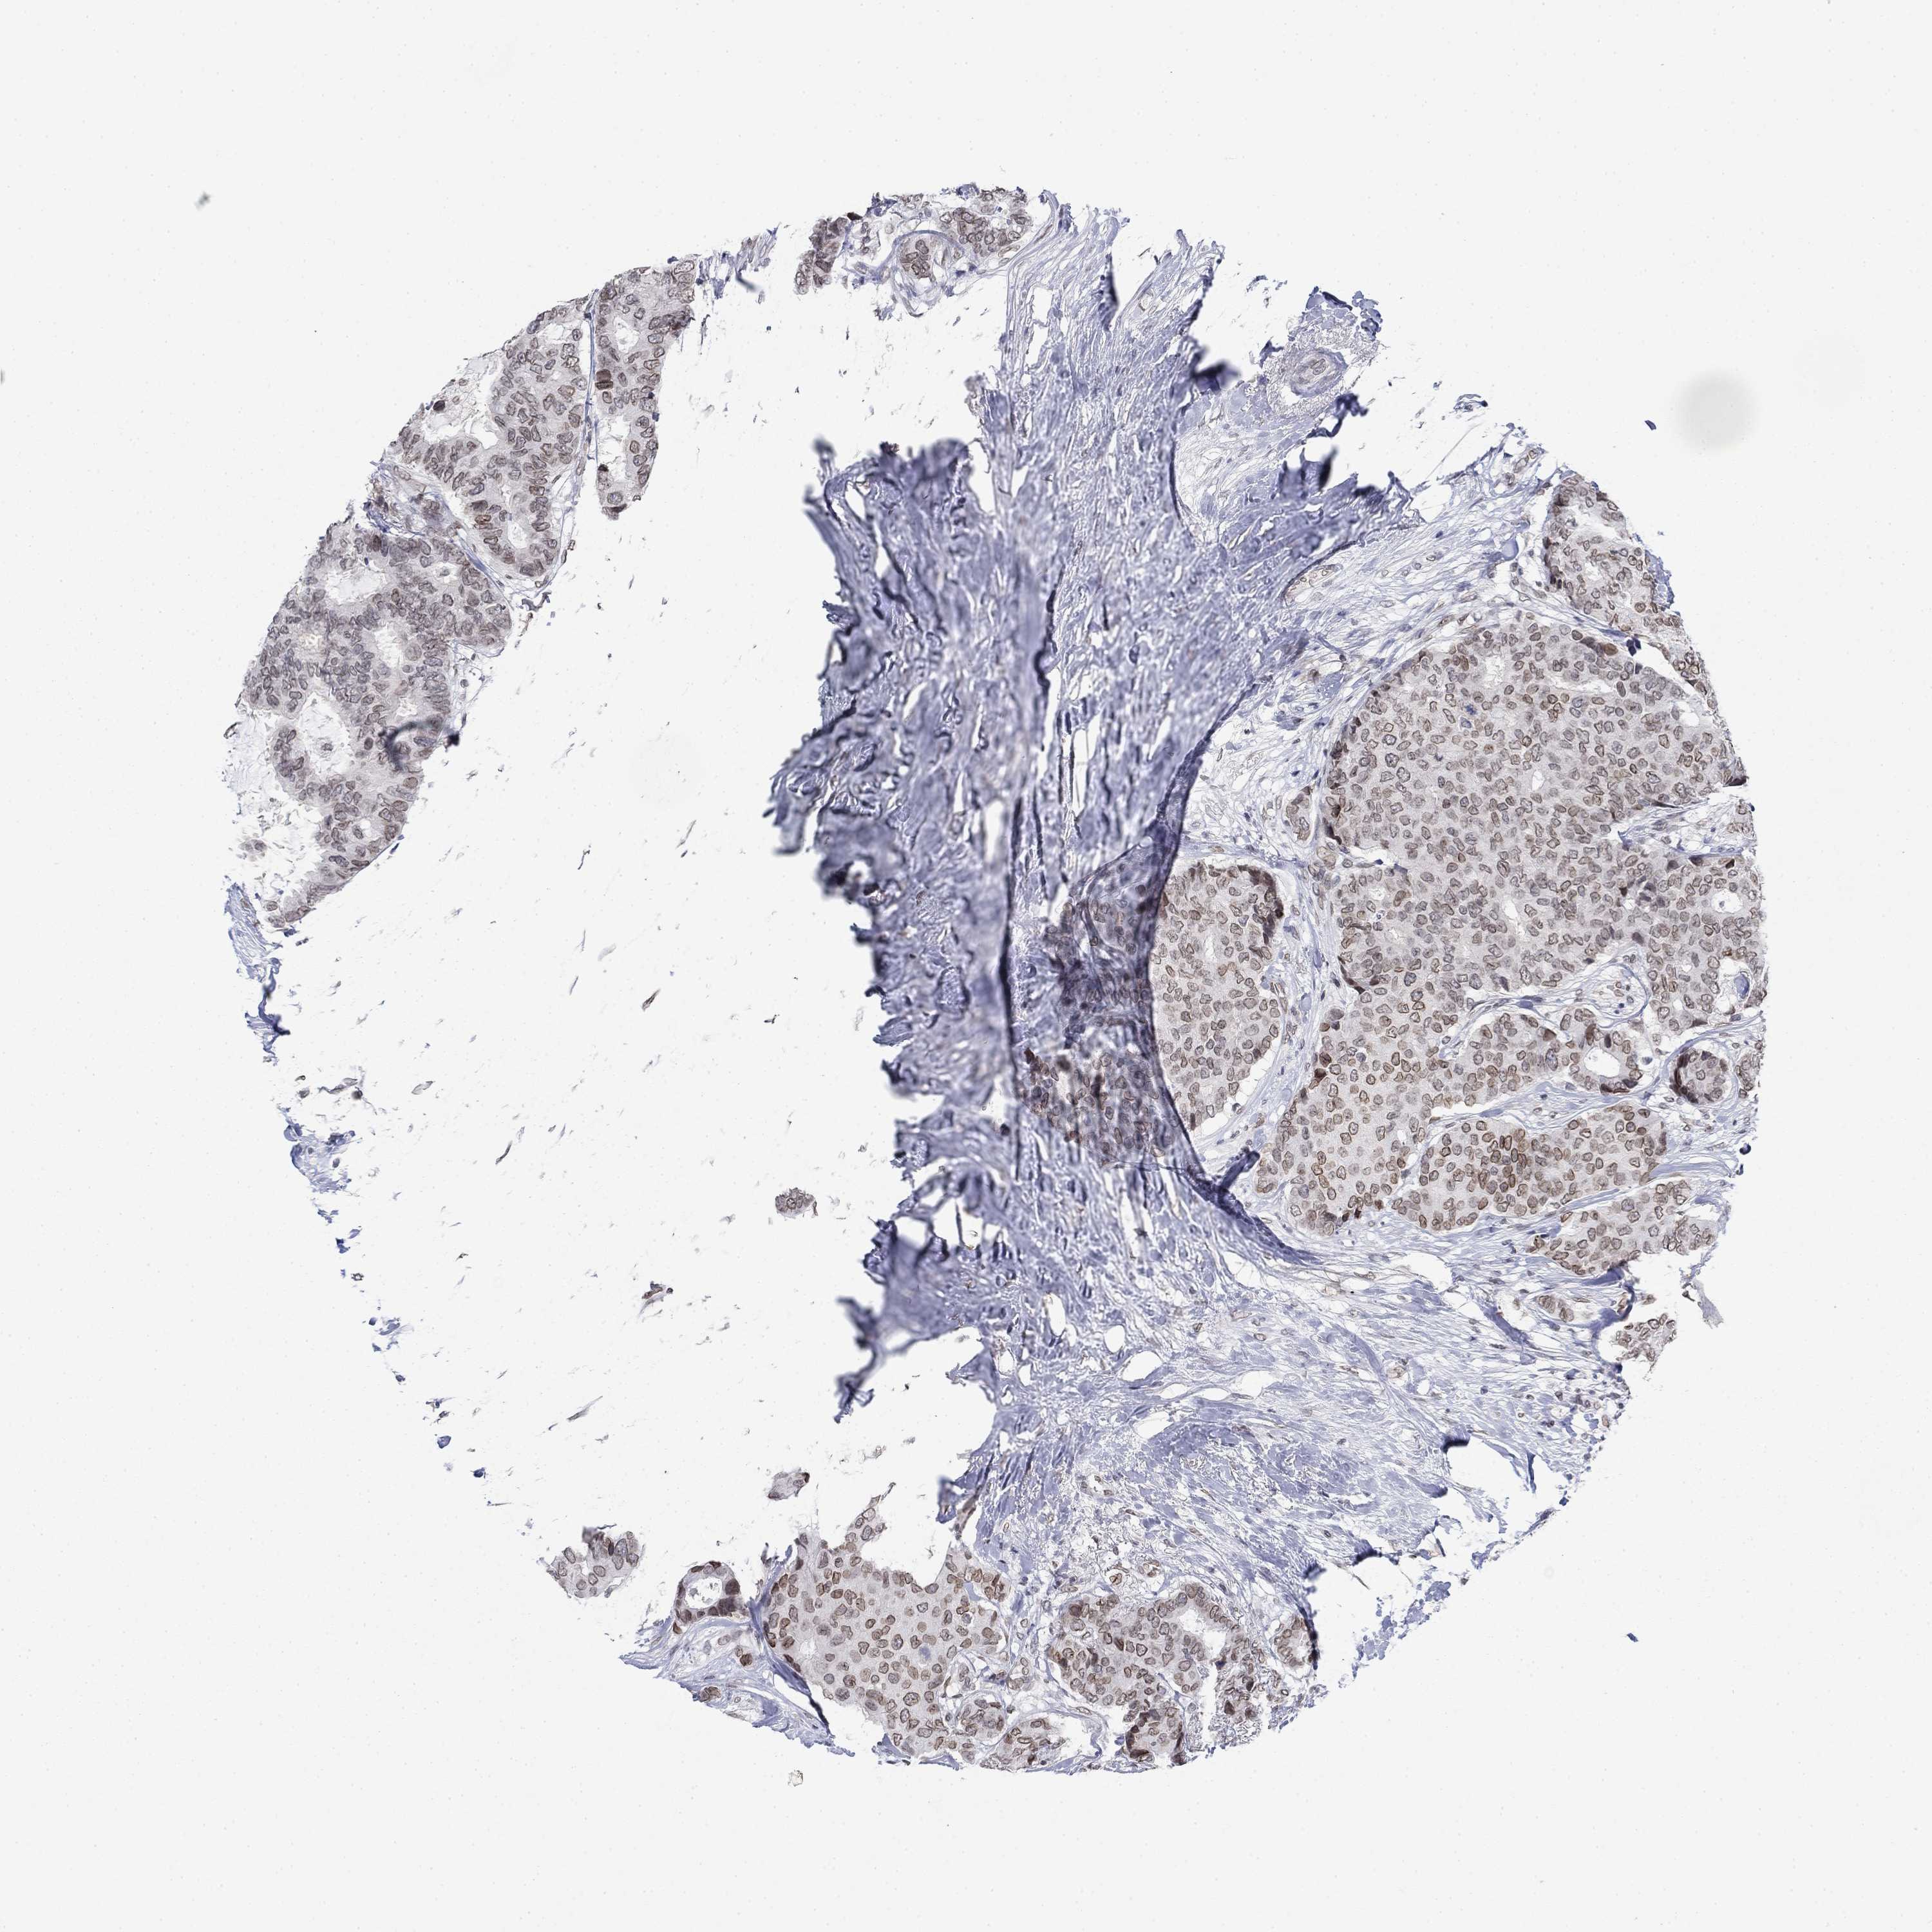

BRCA TCGA BRCA VALIDATION PROTEIN EXPRESSION

ANTIBODIES

AND

VALIDATION